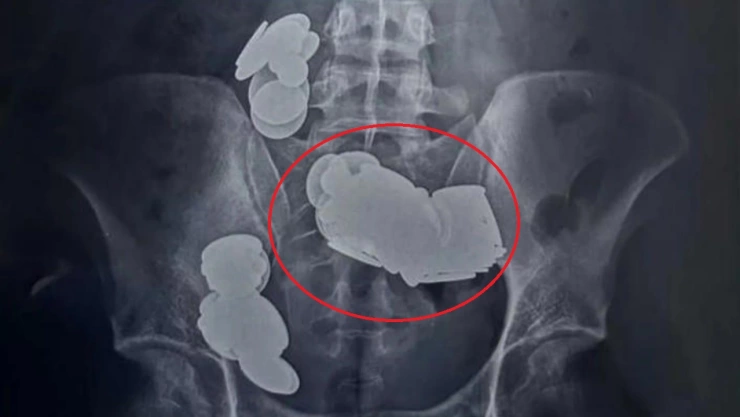

Fue a través de una radiografía de su abdomen, que se pudo observar que en el intestino resguardaba diversos objetos metálicos, y con una tomografía computarizada abdominal, se pudo detectar que tenía un número significativo de ellos obstruyendo sus intestinos, por lo que tuvo que ser llevado de urgencia para una cirugía.

Luego de algunas horas de intervención, el personal médico logró extraer 37 imanes de diversas formas, así como 39 monedas de uno, dos y cinco rupias.

Por si esto no fuera suficiente, durante la cirugía, se descubrió que el metal había formado dos bucles separados en el intestino delgado, provocando una atracción magnética que rompió los órganos internos; no obstante, estos objetos fueron retirados y se logró reconectar las zonas dañadas.